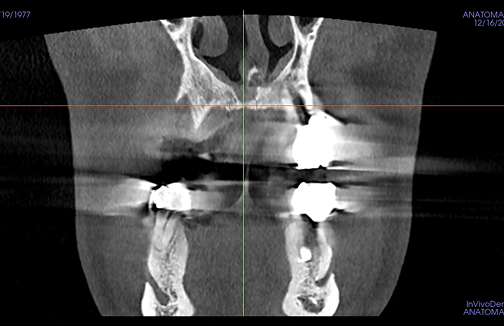

연세준치과는 숙련된 의료진의 경험과 첨단 디지털 장비로

데이터 기반의 과학적인 분석과 예측을 통해

더욱 빠르고 정확한 결과를 제공합니다.

어려운 케이스일수록

자신 있습니다.

당뇨 · 고혈압 등 전신질환 수술을 받으신 분부터 재수술이 필요하신 분들까지.